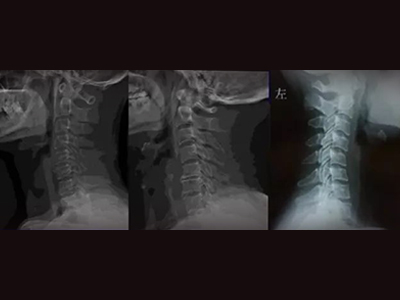

颈椎曲度变直是一种常见的颈椎病变,治疗方法多种多样,包括改善坐姿、颈部锻炼等,患者需根据个体情况选择最适合的方案。